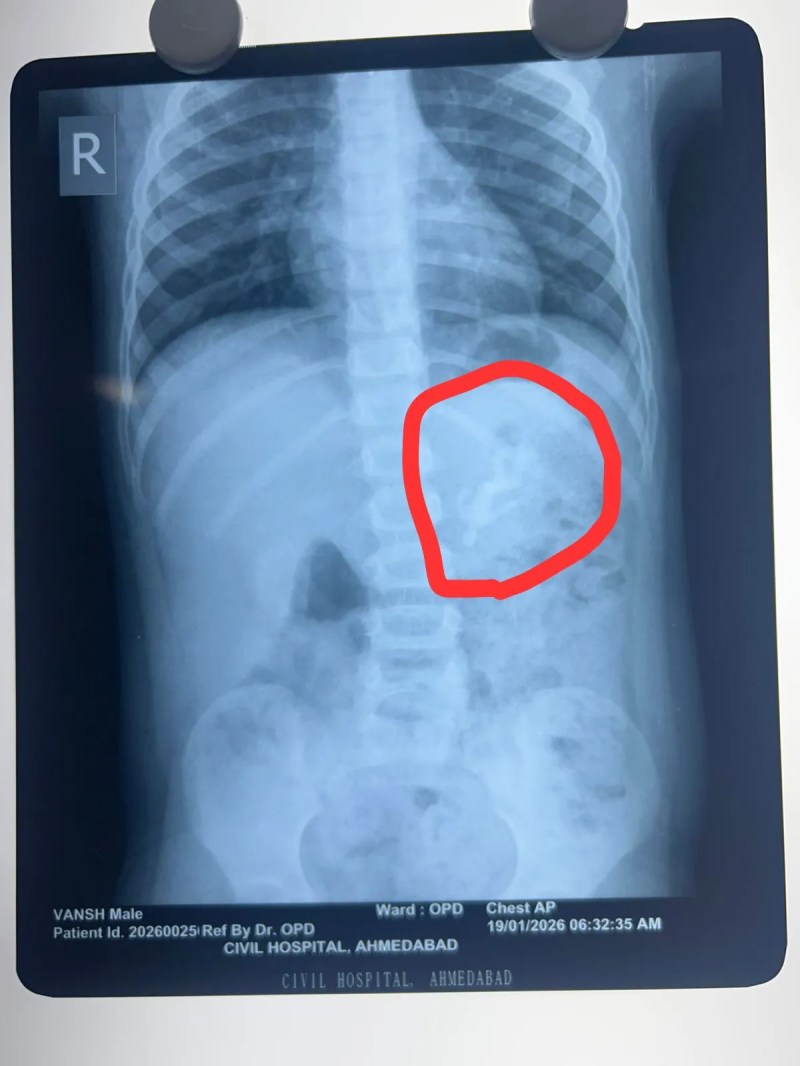

Ahmedabad: शहर स्थित सिविल अस्पताल में चिकित्सकों ने जटिल ऑपरेशन कर डेढ वर्ष के एक बच्चे के पेट से प्लास्टिक का खिलौना निकाला।बताया जाता है कि शहर का एक बच्चा खेलते-खेलते प्लास्टिक का खिलौना निगल गया था। बच्चा खेलते समय अचानक उल्टी करने लगा और उसके चेहरे पर तकलीफ के भाव दिखे। बच्चे की मां को शंका हुई कि बच्चा कोई वस्तु निगल गया है। जांच करने पर पता चला कि खिलौनों में से एक गायब है। परिवार तत्काल उसे शहर के सिविल अस्पताल लेकर पहुंचा। अस्पताल में एक्स-रे में पूरा खिलौना जठर में फंसा दिखाई दिया। चुनौती यह थी कि अन्ननली और जठर के बीच से इतने बड़े खिलौने को सुरक्षित बाहर कैसे निकाला जाए।

अस्पताल के चिकित्सा अधीक्षक एवं पीडियाट्रिक सर्जरी विभागाध्यक्ष डाॅ. राकेश जोशी ने बताया कि एंडोस्कोप के नाजुक उपकरण से खिलौने को पकड़ने का प्रयास करते समय वह बार-बार फिसल रहा था। यदि इसे ज्यादा जोर से खींचा जाता तो वॉल्व को स्थायी नुकसान हो सकता था। अंत में सावधानी से खिलौने के सिर वाले हिस्से को पकड़कर वॉल्व पार कराया गया और बाहर निकाला गया।

डॉक्टरों का कहना है कि यदि यह खिलौना जठर से आगे आंतों में चला जाता तो ब्लॉकेज और आंत फटने का खतरा था। समय पर अस्पताल पहुंचने और चिकित्सकों की कुशलता से बच्चे की जान बच गई। इस जटिल एंडोस्कोपिक सर्जरी में एनेस्थीसिया विभाग की डॉ.श्वेता व उनकी टीम ने सहयोग किया। ऑपरेशन के बाद बच्चा पूरी तरह स्वस्थ है।